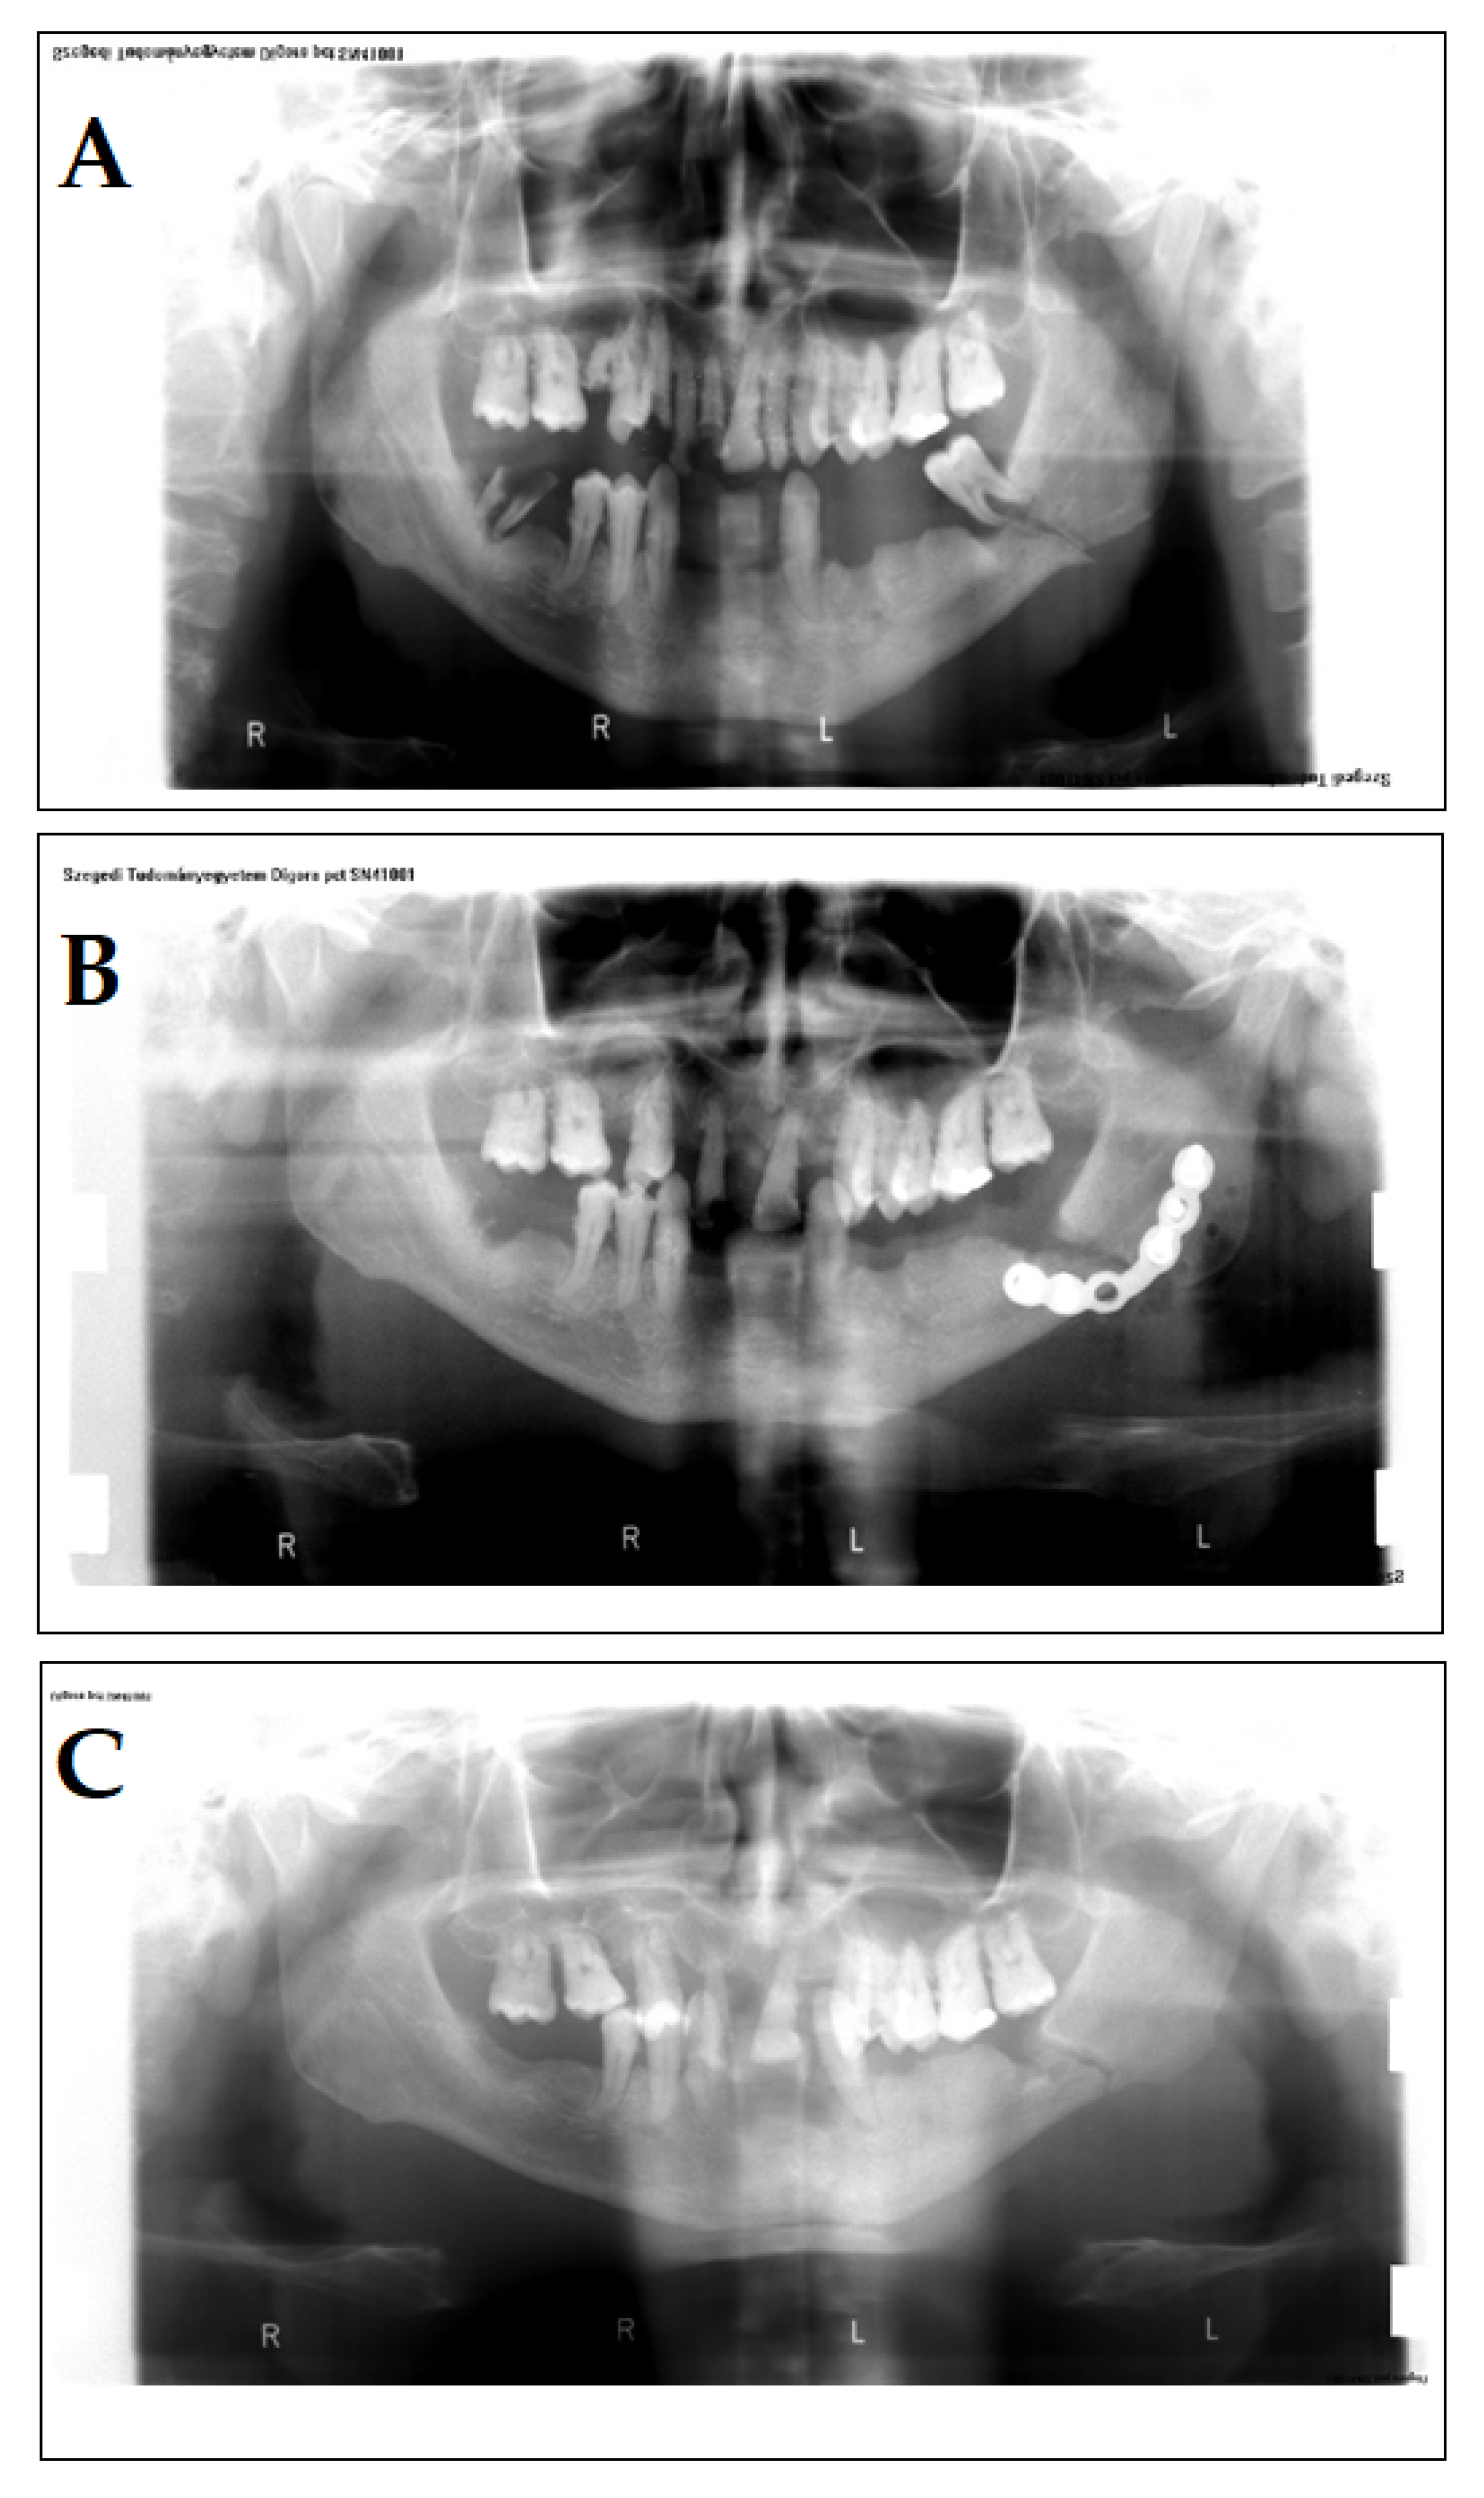

A 40-year-old male patient presented in our clinic with complaints that he attributed to a previous accident. In the past medical history, the patient reported that a wooden log hit his face. The chief complaints of the patients were pain and swelling on the left side of the face, paresthesia on the lower lip from the midline to the left side, and a wound with serosanguineous discharge. A few days previously, he reported seeing his general practitioner; there, the wound was rinsed with Betadine (povidone-iodine) several times; however, healing of the wound was not complete. No underlying disease or pharmacotherapy was found in the patient’s history that would indicate immunosuppression, and he did not receive antibiotics either. On examination, a 5-mm fistula was detected on the skin of the face, in addition to partial trismus. A panoramic X-ray was performed, where a mandibular fracture was identified (Figure 2A). The patient was of lower social standing and had neglected oral hygiene and an incomplete set of teeth (Figure 2A–C).

The surgical therapy of the patient was performed under general anesthesia: the surgeons operated on the submandibular part of the bone, extracted the tooth, which was in the broken-line, and removed the bone sequestra and the inflamed tissue in the process. After checking the occlusion, the broken edges were reponated and an osteosynthesis was performed using a Leibinger-plate (Figure 2B). On the 4th day post-op, the patient was discharged and was prescribed amoxicillin 750 mg/q12h for 5 days and was instructed to return for suture removal. Upon consultation, it was suspected that the adherence of the patient towards taking the prescribed antibiotics was inadequate. The patient came back 6 months later, complaining of swelling and pain on the same part of his face. Partial trismus was once again seen, and on the submandibular part of his face (where the surgical callus was found), a fistula was detected. An incision was made in this area and a sample was taken to be sent to the Department of Bacteriology for examination. While the Gram- and other staining methods (acid-fast, lactophenol blue) were inconclusive, cultivation of the sample in an anaerobic environment (for metholodological details, see Case 1) yielded A. israelii in high colony counts (>105 CFU/ml) as the only isolated pathogen; other anaerobes, facultative anaerobes of fungi were not detected. As A. israelii was the only isolated species and the symptoms of the patient corresponded to the presumptive diagnosis of cervicofacial actinomycosis, histopathology was not performed. The therapy of the patient included 1200 mg/q8h amoxicillin intravenously, and 8 days later, the Leibinger-plate was surgically removed. The surgeons also drained the infected site. The patient was discharged and he was instructed to take amoxicillin 750 mg/q12h for 7 days per os. The patient was continuously observed for a year (monthly for three months and then every three months); however, there were no additional complaints.

Figure 2. Panoramic X-rays of the patient in Case 2. A: Initial status of the patient, lower left molar in the fracture. B: Osteosynthesis with Leibinger-plate. C: Following the removal of the Leibinger-plate, during the healing period.